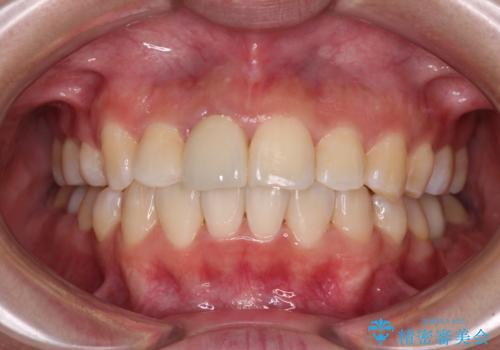

口元の突出感のない、すっきりとした仕上がりとなりました。